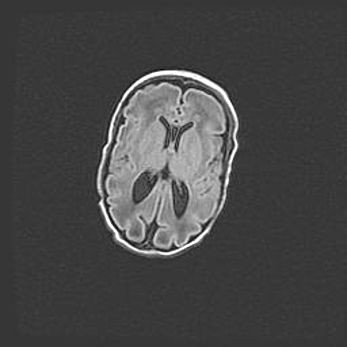

Лейкомаляция с кистозно-глиозной дегенерацией головного мозга.

Возраст: 2 месяца 25 дней

Вес: 6400 г

Окружность головы: 40 см

Срок гестации: 41 неделя

Лейкомаляцию относят к ишемически-гипоксическим повреждениям головного мозга, диагностируемым у новорожденных. При лейкомаляции в головном мозге обнаруживают очаги некроза, возникшие после тяжелой гипоксии и нарушения кровотока. В процессе морфогенеза очаги проходят три стадии: 1) развития некроза, 2) резорбции и 3) формирования глиозного рубца или кисты. Перивентрикулярная лейкомаляция (ПЛ) встречается примерно в 12% случаев среди новорожденных, обычно – у недоношенных детей, причем, частота ее зависит от массы, с которой младенец появился на свет. Наибольшее число малышей страдает лейкомаляцией, если масса при рождении 1500-2500 г.